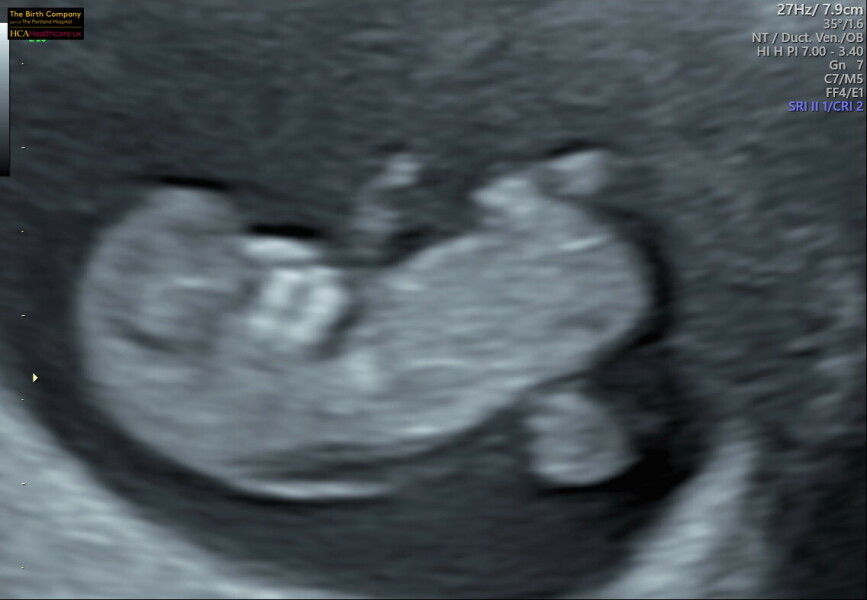

I have been so busy with appointments. I had my last EPU scan on Thursday all looked good. Then booking appointment Friday and yesterday I did the NIPT test. I know some people decided to wait but as I'm 39 and my anxiety has been so high I wanted to do it early. I'm glad I did because my dating scan won't be til almost 14 weeks. I'm nervous about the NIPT results but hopefully will be able to chill a bit more in the next couple of weeks. I do feel like I've started to shift my thinking a bit past first trimester panic after loss and am feeling more connected to the baby. The NIPT came with a scan, was lovely seeing the little wiggler twice in one week.

@WolfMother326 such a cute pic. Congrats :)

Beautiful little bean @WolfMother326 😍